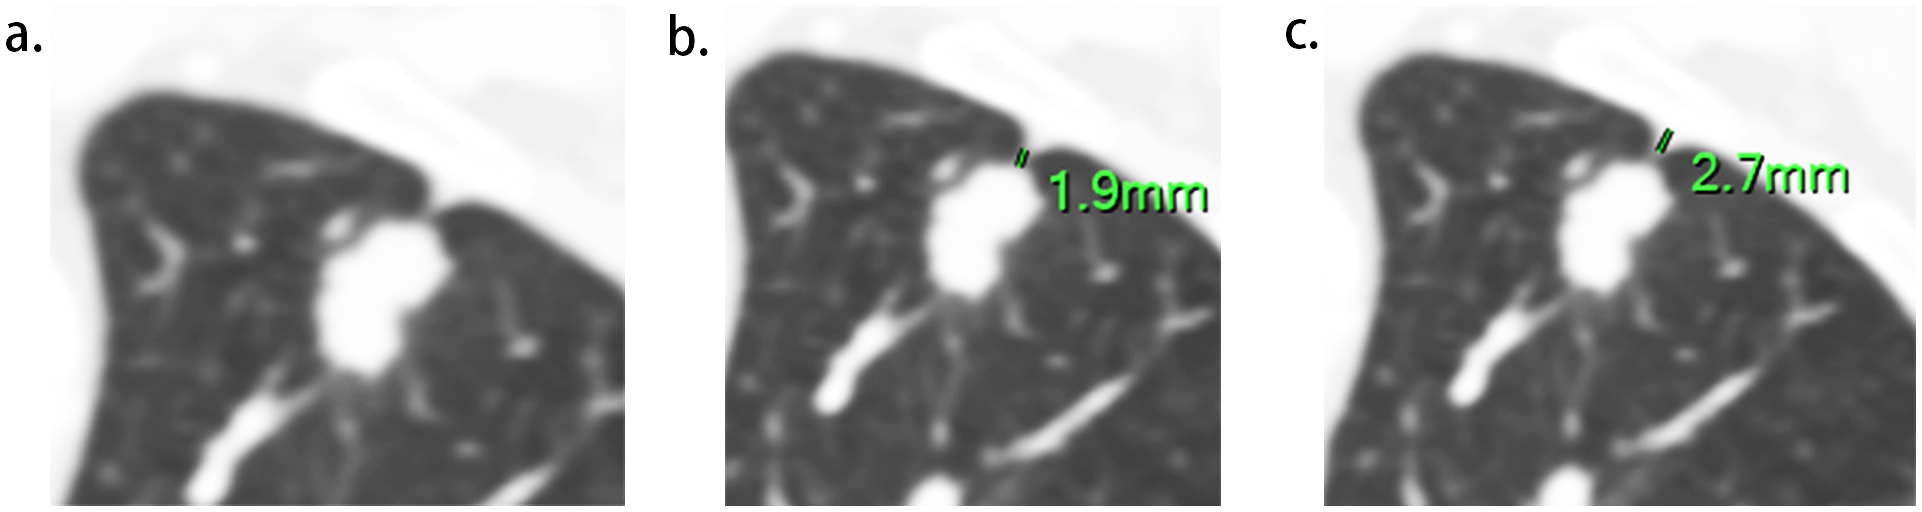

Figure 2

Measurement of LPT (the length of Pleural tag) and DPI (depth of pleural indentation). (A), The slice with the shortest LPT. (B), LPT, measured from the tumor margin to the retracted pleura. (C), DPI, measured by the distance of pleural indentation.

Two radiologists (experienced in diagnosing lung cancers and blind to the status of PI), independently reviewed all CT images on the workstation. We selected the shortest distance from the tumor margin to the pleura as a criterion to identify the target pleural tag from multiple instances. This approach aligns with standard practices in pathology departments and reduces discrepancies between target PT on CT and the actual pleural sites, as pathologists often select slices where lesions abut or are close to the pleura to evaluate the status of pleural invasion. The length of PT (LPT), defined as the shortest distance from the tumor edge to the retracted pleura, was measured on lung windows (window level: -600 HU, window width: 1600 HU) (Figures 2A, B), and PT with shorter LPT was selected by the observers as a priority for further evaluation. On the slice with the minimum LPT, they assessed the depth of pleural indentation (DPI) (Figure 2C), iodine concentration (IC), the presence of pleural thickening, tumor protrusion and the presence of cord-like PT. A region of interest (ROI) was drawn freehand to cover the ipsilateral half of the lesion on mediastinal windows (window level: 40 HU, window width: 350 HU) (Figure 3A), avoiding areas of calcification, obvious necrosis, and large vessels. Lesion IC in the ROI and IC in the center of the aorta was automatically calculated on iodine uptake images (Figure 3B). Normalized IC (NIC) was calculated as the ratio of lesion IC to aorta IC. The presence of pleural thickening was diagnosed when the pleura was thicker than adjacent normal pleura or when soft tissue opacity was observed at the pleural end of PT on mediastinal windows (Figure 3C). Tumor protrusion was identified by wedge-shaped or triangular opacities extending from the tumor margins to the PT (Figure 3D), while cord-like PT was defined as a PT thicker than 2 mm (Figure 3E). The ratio of LPT to DPI was also calculated. Multiple PTs to multiple types of pleura was defined when the tumor with multiple PTs involving more than one types of pleura (costal, fissure, mediastinum, diaphragm) (20)(Figures 4A–C).